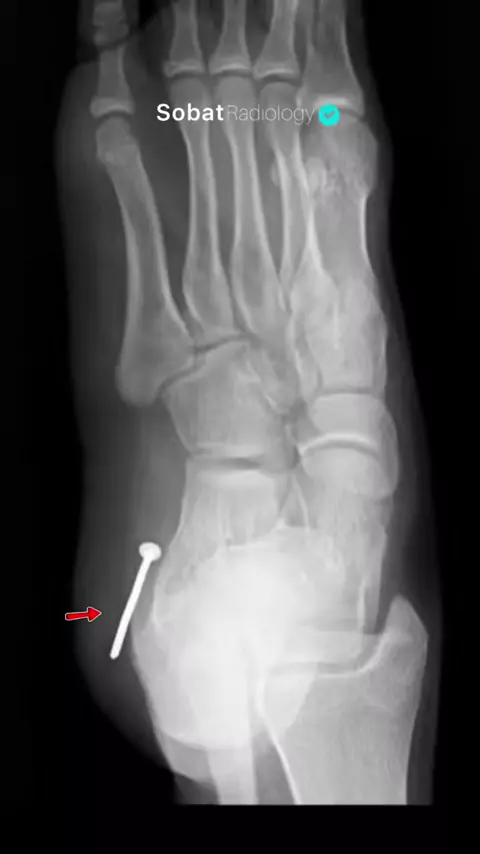

PUT THE ANSWER ON THE COMMENT!!! #pathology #anatomy #xray